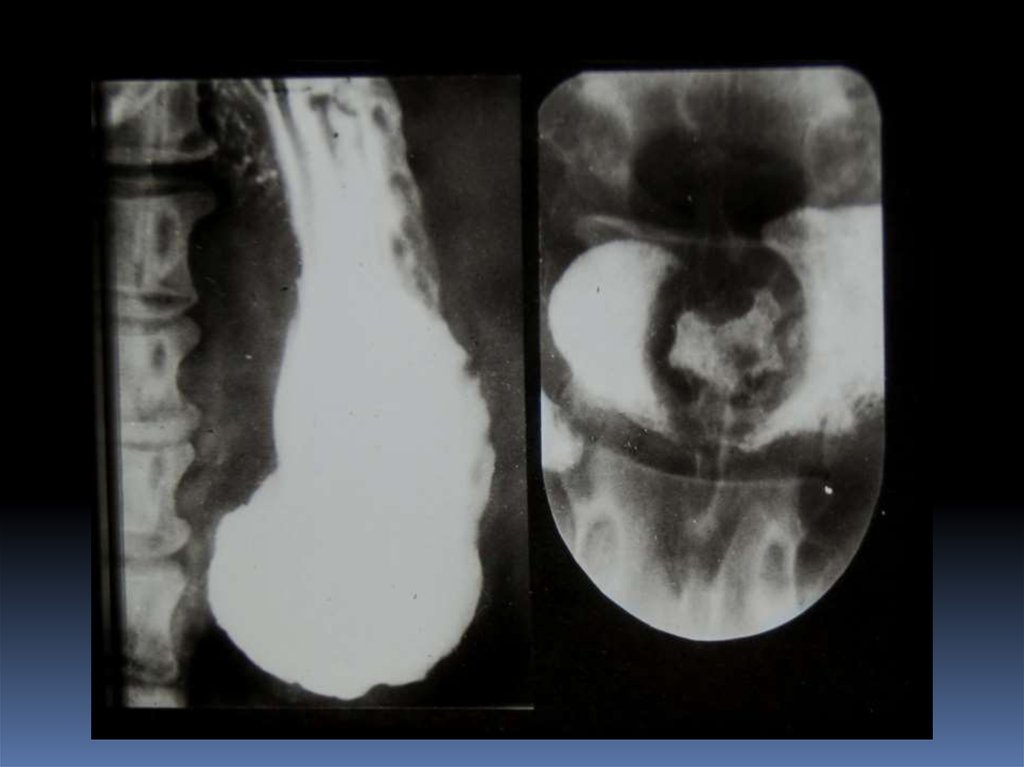

17. Классификация рака органов ЖКТ

1. Экзофитная форма:

2. Эндофитная форма:

узловая форма;

диффузноинфильтративная

форма;

полипоподобная

чашеподобная форма. инфильтративноязвенная.

3. СМЕШАННАЯ ФОРМА – 10-15%